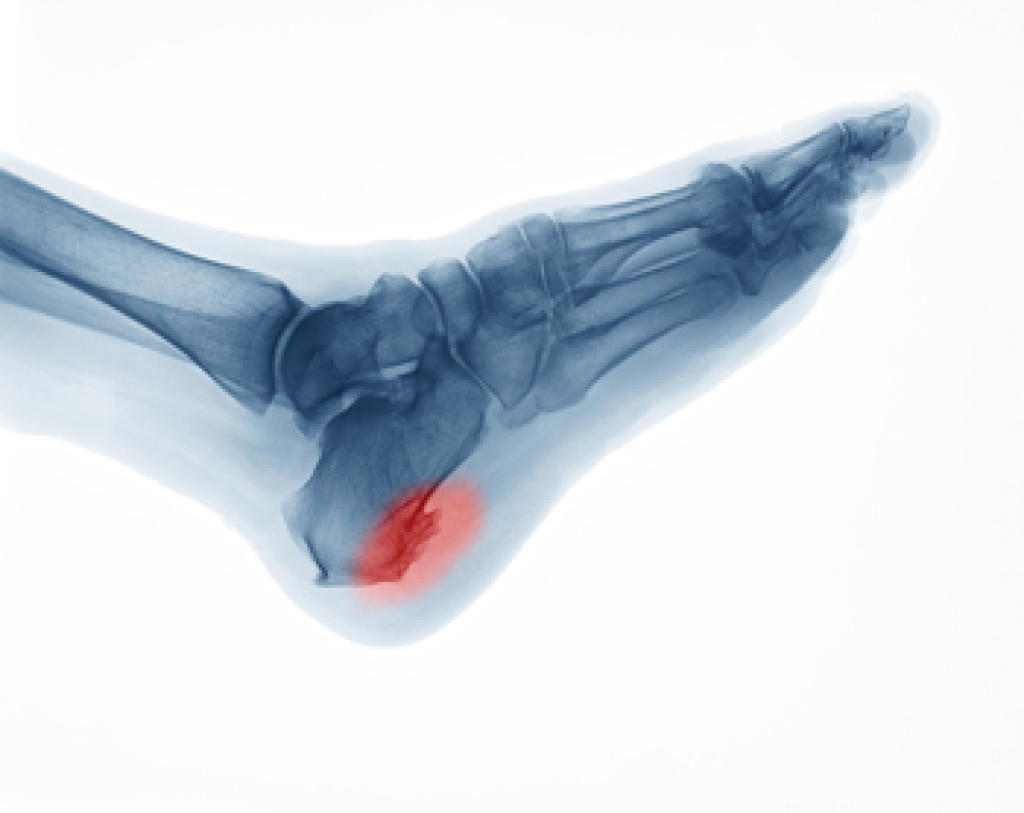

For individuals living with diabetes, maintaining foot care takes on paramount importance. Elevated blood sugar levels can lead to nerve damage and reduced blood flow in the feet, making them vulnerable to infections and slow healing. Regularly inspecting the feet for any cuts, blisters, or sores, can help to prevent infections. It is helpful to moisturize the feet but avoid applying lotion between the toes. Wearing well-fitting shoes made from breathable materials may help to ensure maximum comfort. It is beneficial to choose seamless socks that can prevent friction. Trimming the nails straight across can help to avoid ingrown nails, and elevating the feet while sitting may promote healthy circulation. Prioritizing your foot health is crucial to having a comfortable and active life with diabetes. If you have diabetes, it is strongly suggested that you are under the care of a podiatrist who can help you to manage this serious condition.

Diabetes affects millions of people every year. The condition can damage blood vessels in many parts of the body, especially the feet. Because of this, taking care of your feet is essential if you have diabetes, and having a podiatrist help monitor your foot health is highly recommended.

It is always best to inform your healthcare professional of any concerns you may have regarding your feet, especially for diabetic patients. Early treatment and routine foot examinations are keys to maintaining proper health, especially because severe complications can arise if proper treatment is not applied.